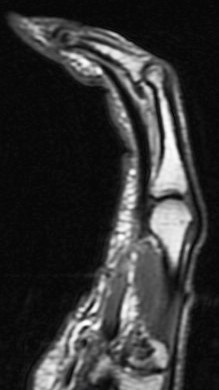

Figure 3 for case A2 pulley rupture finger (RID2437)

Figure 3

Imaging in flexion helps bring out this abnormality. The hand surgeon specifically requests it now. Also I ask the technologist to always include an adjacent normal finger for comparison.

A2 pulley rupture finger (RID2437)